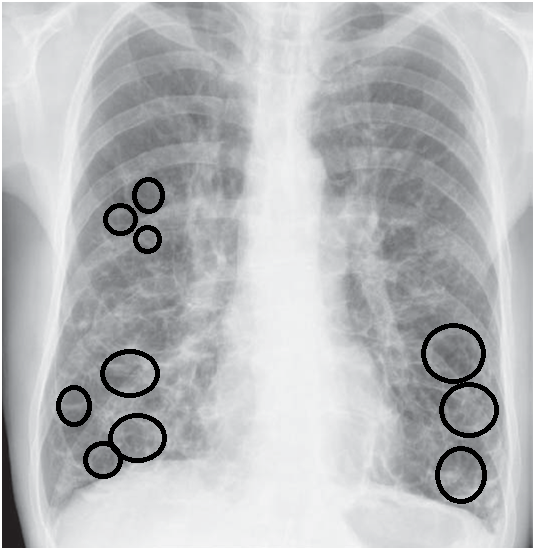

Chest X-Ray Showing Bronchiectasis . Diagnosis of bronchiectasis is usually made using chest computed tomography (ct) scan, the current gold standard method. Chest radiography is usually the initial study performed in suspected bronchiectasis. Imaging plays a pivotal role in the diagnosis of bronchiectasis. Signs in severe disease include tram lines and ring shadows. Findings include bronchial diameter exceeding that of the adjacent pulmonary artery and lack of normal tapering of terminal bronchioles as they course toward the lung periphery.